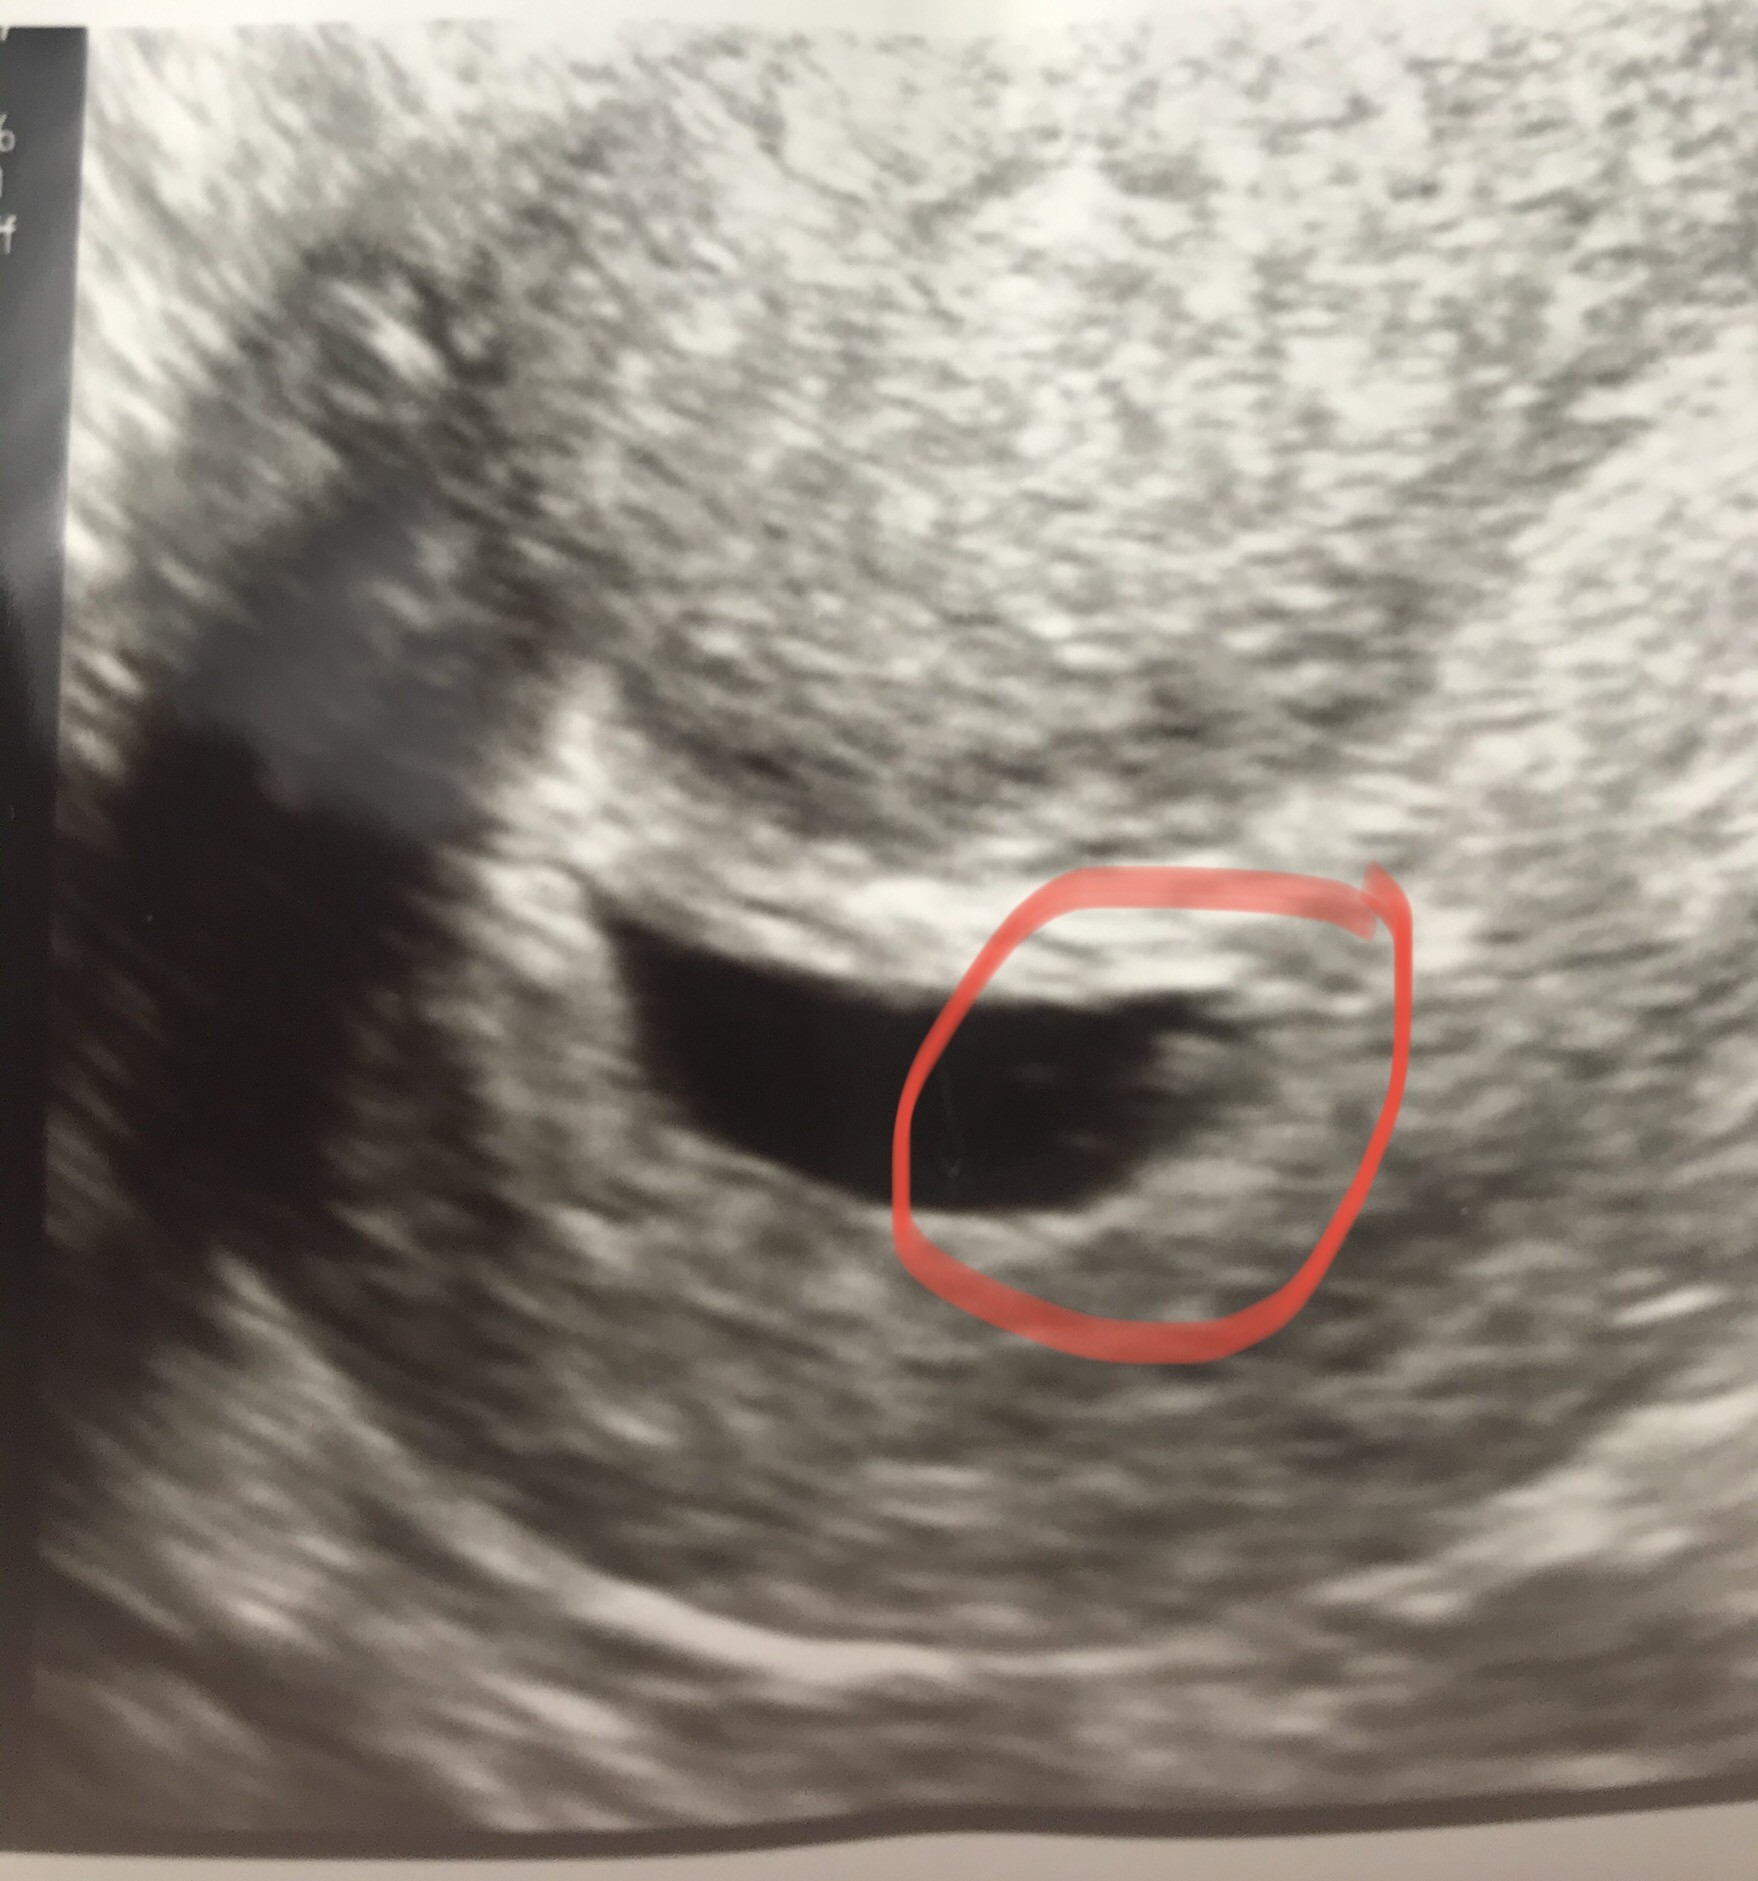

Dziś miałam wizytę . Zarodek widoczny , widziałam tez serducho jak bije 😍 nie słyszałam niestety bo pani dr powiedziała ze jej sprzęt dobry wzięli do naprawy i dali zastępczy przed poptopowy 🤣

Fasolek ma 3 mm i jesteśmy w 6 tyg ciąży 🙈